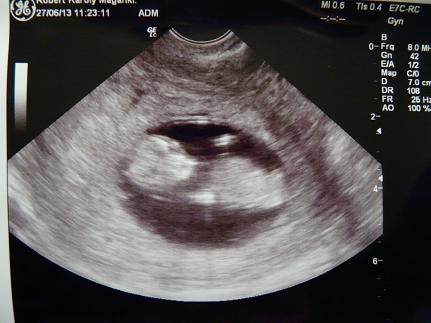

bár amúgy is. kidobta az uh képet?